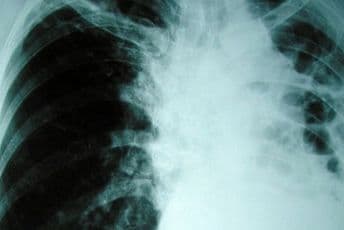

"U pitanju je porodična epidemija, u kojoj je oboljelo šestoro djece iz dvije osnovne škole, a bolest je registrovana polovinom prošlog mjeseca. Trenutno se vrši testiranje učenika iz odjeljenja u kojima borave oboljela djeca, kao i njihovih nastavnika i do kraja ove nedjelje završavamo jednu školu, dok je testiranje druge planirano za sljedeću nedjelju", navela je Iković.

U Novom Pazaru godišnje od tuberkuloze oboli oko 50 osoba, a tokom prošle godine potvrđeno je oko 30 takvih slučajeva.